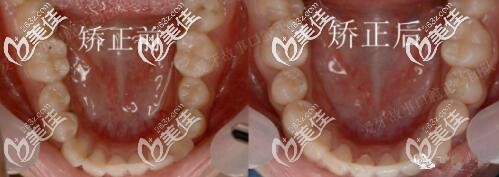

图四前后牙弓对比

矫正用了1年半,地包天明显改善,牙弓也扩开了。正畸期间口腔护理很重要,如果出现了口腔有异味或炎症,就要隔两到三天使用牙套清洁片把牙套泡一泡,必要时可用酒精棉片对牙套进行消毒。